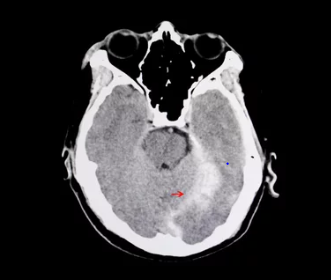

뇌출혈이 의심되는 경우, 즉시 의료 기관을 방문하여 정밀 진단을 받는 것이 중요합니다. 컴퓨터 단층촬영(CT)이나 자기공명영상(MRI) 검사를 통해 뇌 내부의 출혈 여부를 확인할 수 있으며, 필요한 경우 적절한 치료를 받을 수 있습니다.